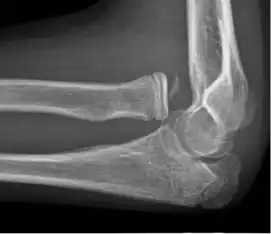

- Elbow

![X-ray of ventral dislocation of the radial head. There is calcification of annular ligament, which can be seen as early as 2 weeks after injury.[52]](./X-ray_of_ventral_dislocation_of_the_radial_head_with_calcification_of_annular_ligament.jpg)